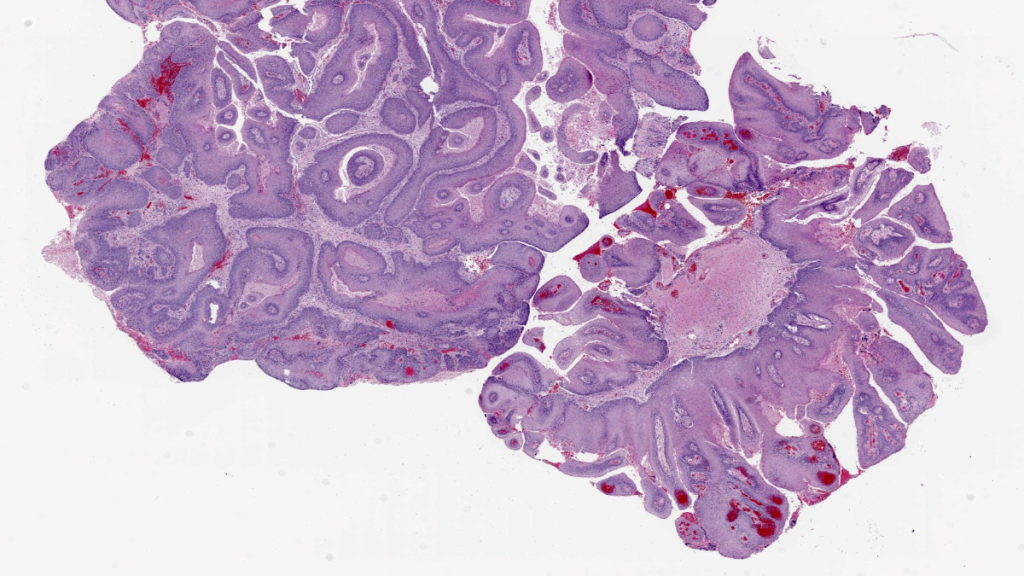

Recurrent Respiratory Papillomatosis (RRP) is a rare and debilitating neoplastic condition caused by chronic infection with human papillomavirus (HPV) types 6 or 11. It leads to the growth of papillomas in the upper aerodigestive tract. Currently, there are limited approved medical treatments available for RRP, necessitating repeated surgical procedures to maintain voice and airway function. PRGN-2012 is an immune-therapeutic utilizing a gorilla adenovirus, designed to enhance the immune response against HPV types 6 and 11.

In-depth investigations also revealed important correlations. Patients who responded well to the treatment showed reduced baseline expression of papilloma-associated HPV genes, along with heightened interferon responses and increased expression of CXCL9 and CXCL10, which are key chemokines. Additionally, responders displayed greater infiltration of T cells into the papillomas. On the contrary, nonresponders exhibited higher levels of HPV and CXCL8 gene expression, increased presence of neutrophilic cells, and reduced T cell infiltration in the papillomas. These findings suggest that the expression of papilloma-associated HPV genes may influence interferon signaling and chemokine profiles within the tumor microenvironment, ultimately impacting the clinical response to therapeutic HPV vaccination in individuals with respiratory papillomatosis. This research highlights the potential for further development of PRGN-2012 as a promising treatment option for patients affected by RRP.